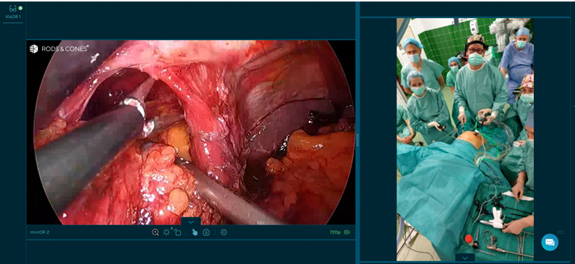

Po raz pierwszy w historii Rydygiera, zabieg przeprowadzany na szpitalnym bloku operacyjnym w Nowej Hucie transmitowany był w czasie rzeczywistym do ośrodków medycznych w 15 krajach Europy oraz do 4 szpitali w Polsce.

Skomplikowaną operację lewostronnej hemikolektomii, której poddany został 68 letni Pacjent z nowotworem odbytnicy, wykonywał i komentował dla obserwatorów prof. Andrzej Budzyński, Ordynator Oddziału Chirurgii Ogólnej i Onkologicznej Szpitala Rydygiera, w asyście 3 osobowego zespołu szpitalnych operatorów.

Tę strategię docenili uczestnicy warsztatów, obserwujący ponad 3,5 godzinną operację prowadzoną przez prof. Budzyńskiego, którzy dzięki transmisji live surgery mieli możliwość zadawania pytań, a tym samym zyskali szansę teoretycznego współtworzenia koncepcji dla kolejnych etapów prowadzonego zabiegu.